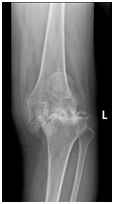

骨性关节炎早期主要累积关节表面软骨,如果在症状较轻的时候就及时干预,那么还是有很大的机会让骨性关节炎远离我们。在关节炎早期,服用NSAID类药物是可以比较明显的缓解症状,但是中晚期往往需要手术干预,休息时和夜间持续疼痛是骨关节炎患者外科手术治疗的适应症,尽管年龄不是手术治疗的禁忌症,但患者的总体情况是一个重要因素,尤其是老年骨关节炎晚期患者,往往需要行关节置换术,人工关节置换术已成为治疗关节严重病变的主要手段之一,被誉为20世纪骨科发展史重要里程碑之一。